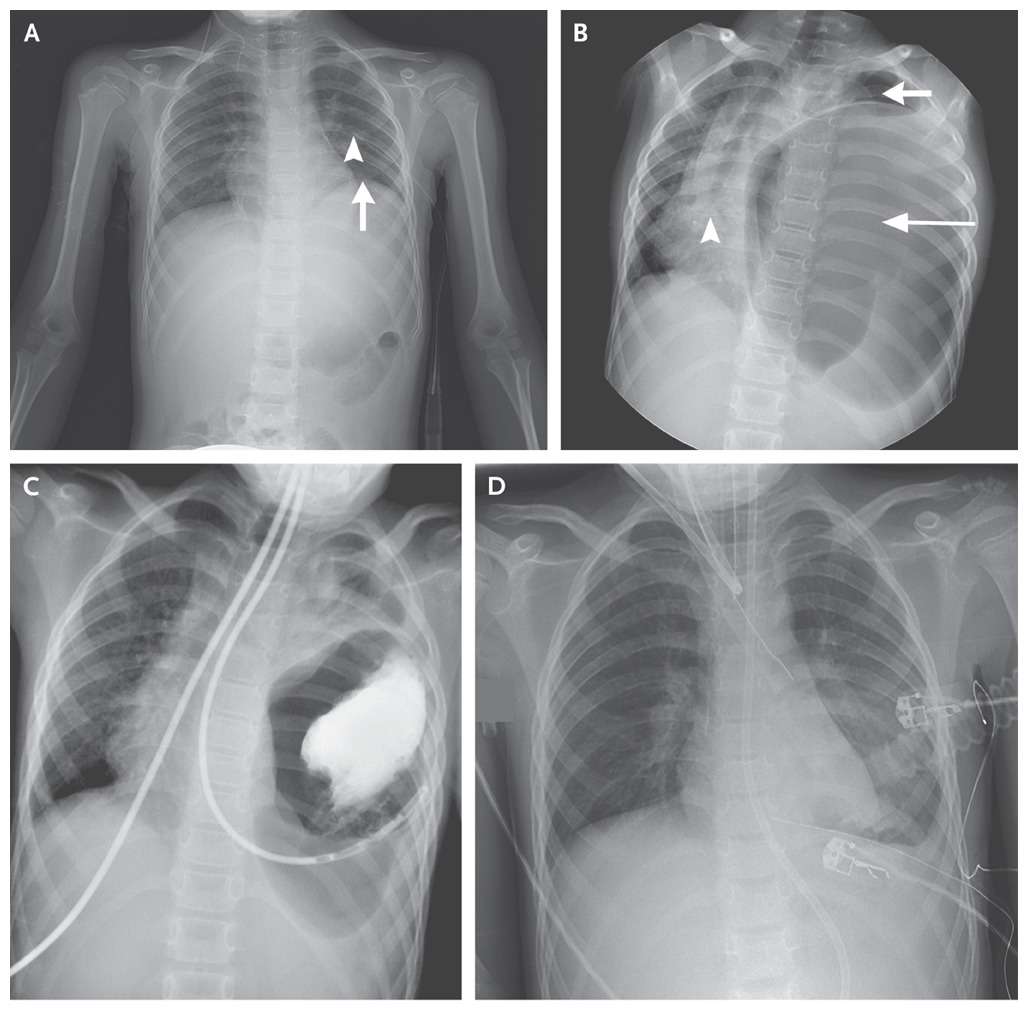

The patient had a left posterolateral diaphragmatic rupture and underwent emergency surgery, during which the stomach, spleen, left kidney, and part of the transverse colon were repositioned within the abdomen and the rupture repaired.

A postoperative chest radiograph showed reexpansion of the left lung (Panel D). The patient had a smooth recovery and was discharged home 10 days after the surgery.